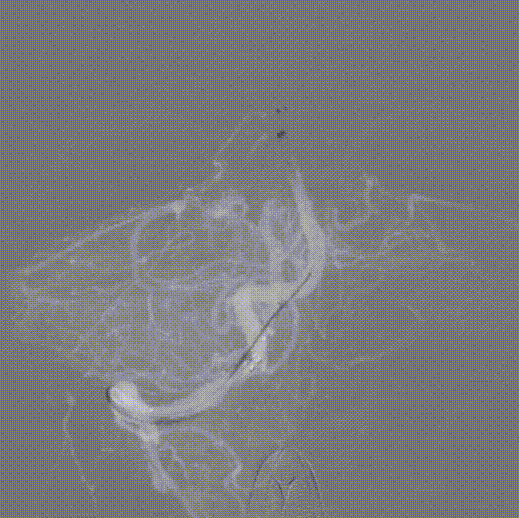

导管到位后造影。

内衬5F 125 通桥银蛇®颅内支持导管,将经桡神经介入导管上高至V4段。

4-20 通桥蛟龙®取栓支架+5F 125 通桥银蛇®颅内支持导管,抽拉结合取栓开通。

取栓后造影。

撤管后造影见椎动脉正常显影,无夹层无痉挛。